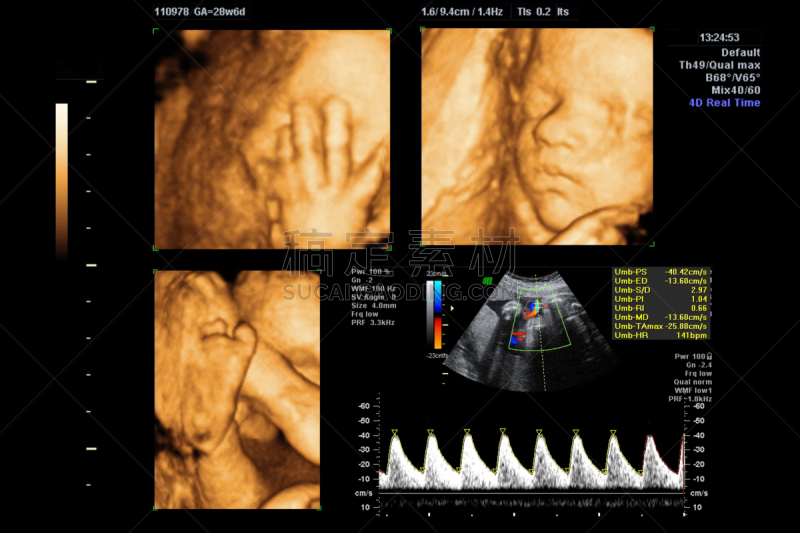

20周胎儿超声检查详情

胎儿心脏的超声检查详情

胎儿心脏的超声检查详情

胎儿心脏的超声检查。详情